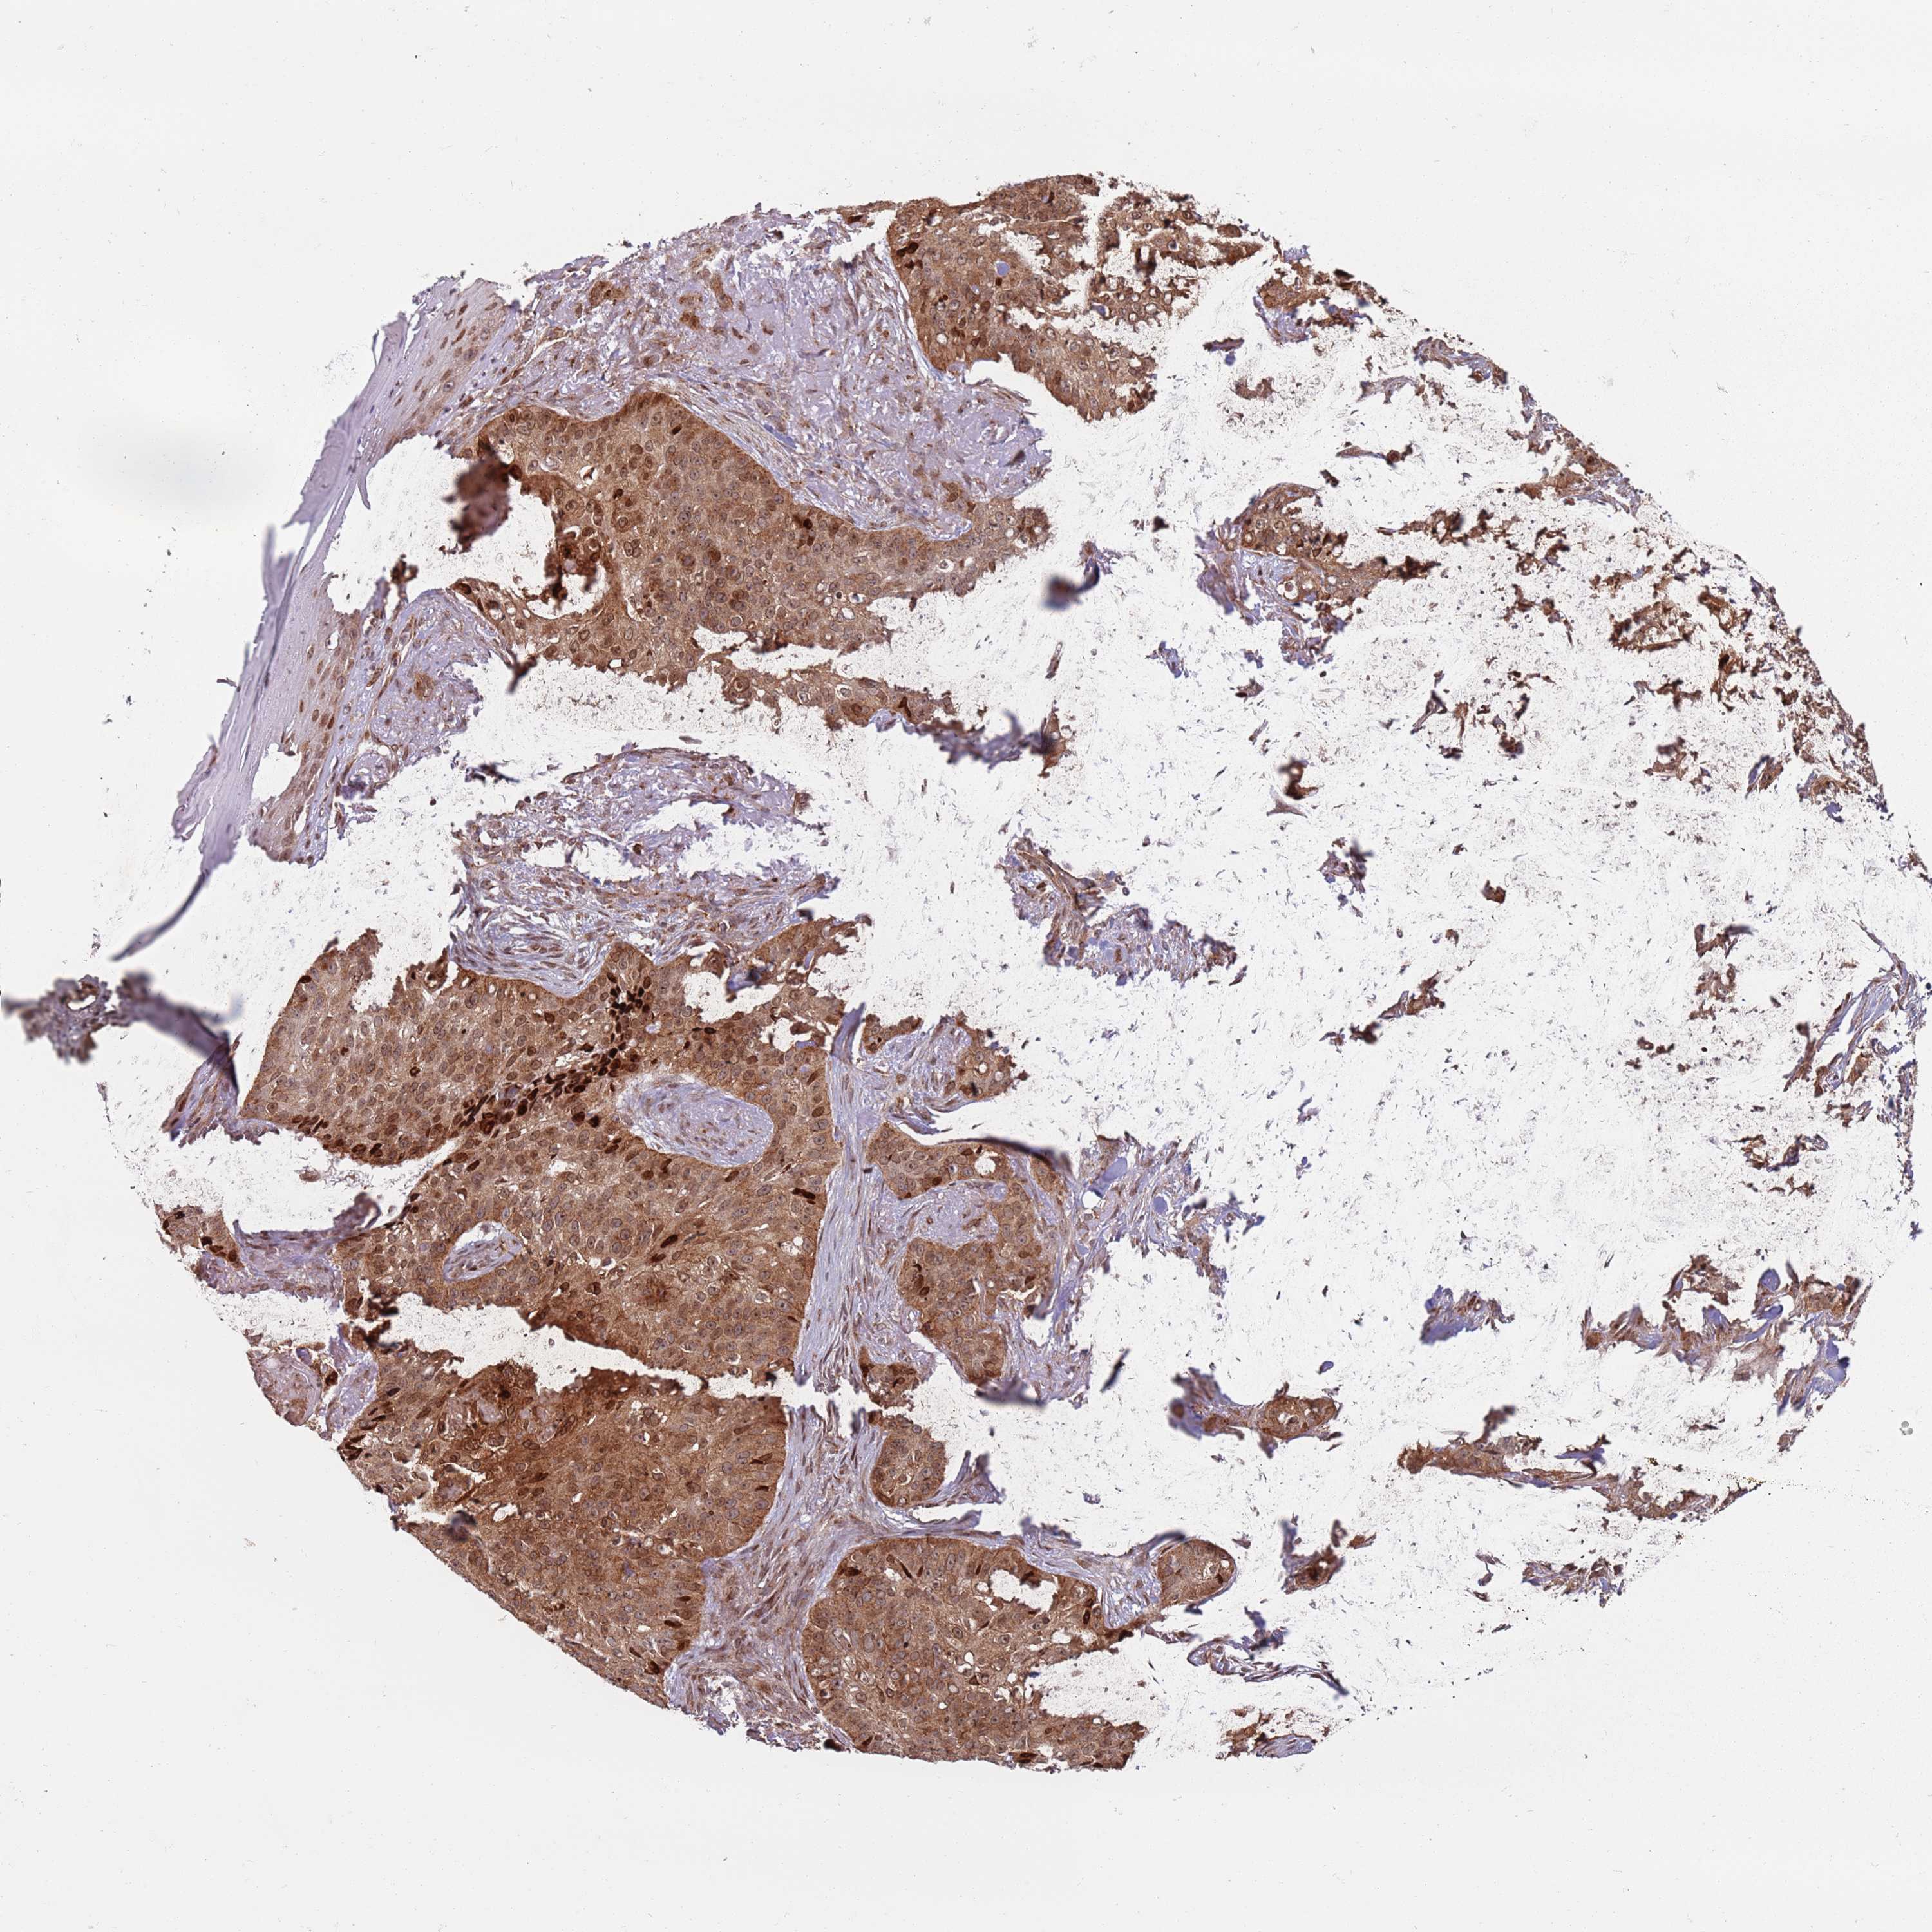

CANCER SKIN CANCER Show tissue menu

Basal cell and squamous cell cancer

SKIN CANCER - Protein expressioni

A mouse-over function shows sample information and annotation data. Click on an image to view it in a full screen mode. Samples can be filtered based on level of antibody staining by selecting one or several of the following categories: high, medium, low and not detected. The assay and annotation is described here.

Each image is clickable and will lead to virtual microscopy that enables deeper exploration of all samples and also displays staining intensity scores, fraction scores and subcellular localization as well as patient and tissue information for each sample.

Antibody HPA046084

Staining

High

Strong

Quantity

Location

Basal cell carcinoma